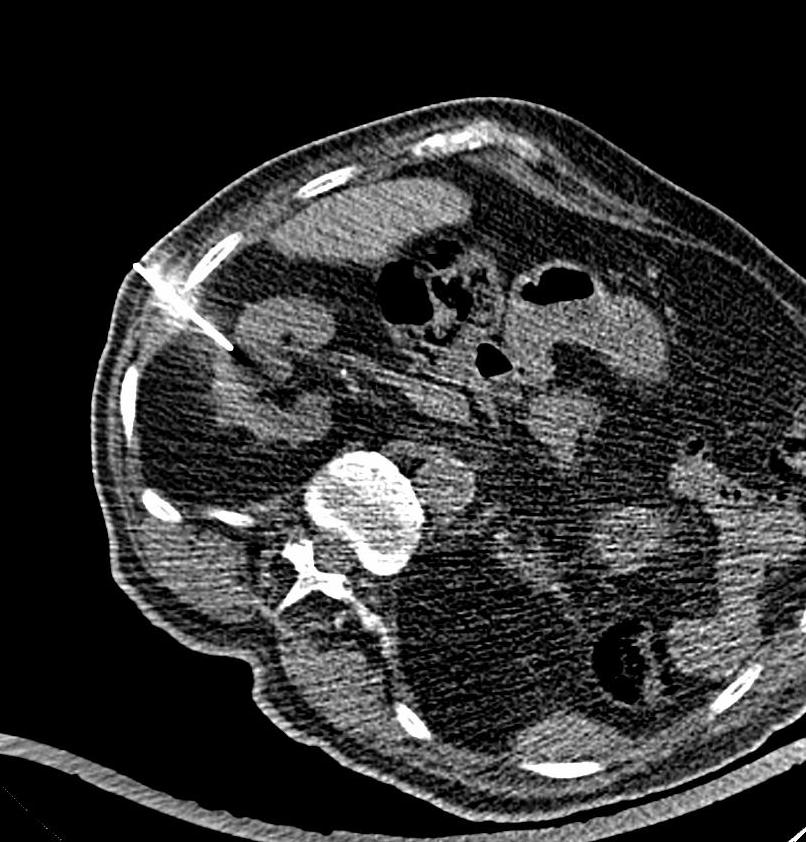

Je nach Fragestellung müssen Sie vor der Untersuchung Kontrastmittel trinken, damit der Magen- Darm- Bereich besser dargestellt werden kann. Die Kontrastmittelmenge beträgt meist 1 Liter, den Sie über einen Zeitraum von etwa 1 Stunde trinken müssen. Bei manchen Untersuchungen ist die Gabe von Kontrastmittel über eine Vene (zusätzlich) erforderlich. Manche Erkrankungen erfordern auch eine Kontrastmittelgabe über den Enddarm, hierfür müssen Sie zu Hause keine besonderen Vorbereitungen treffen. Dabei wird Ihnen über ein Darmrohr ein Liter verdünntes jodhaltiges, vorgewärmtes Kontrastmittel verabreicht, nachdem der Arzt den Enddarm untersucht hat.

Die Untersuchungsdauer beträgt zwischen 20 Minuten bis 90 Minuten bei oraler Kontrastmittelgabe.